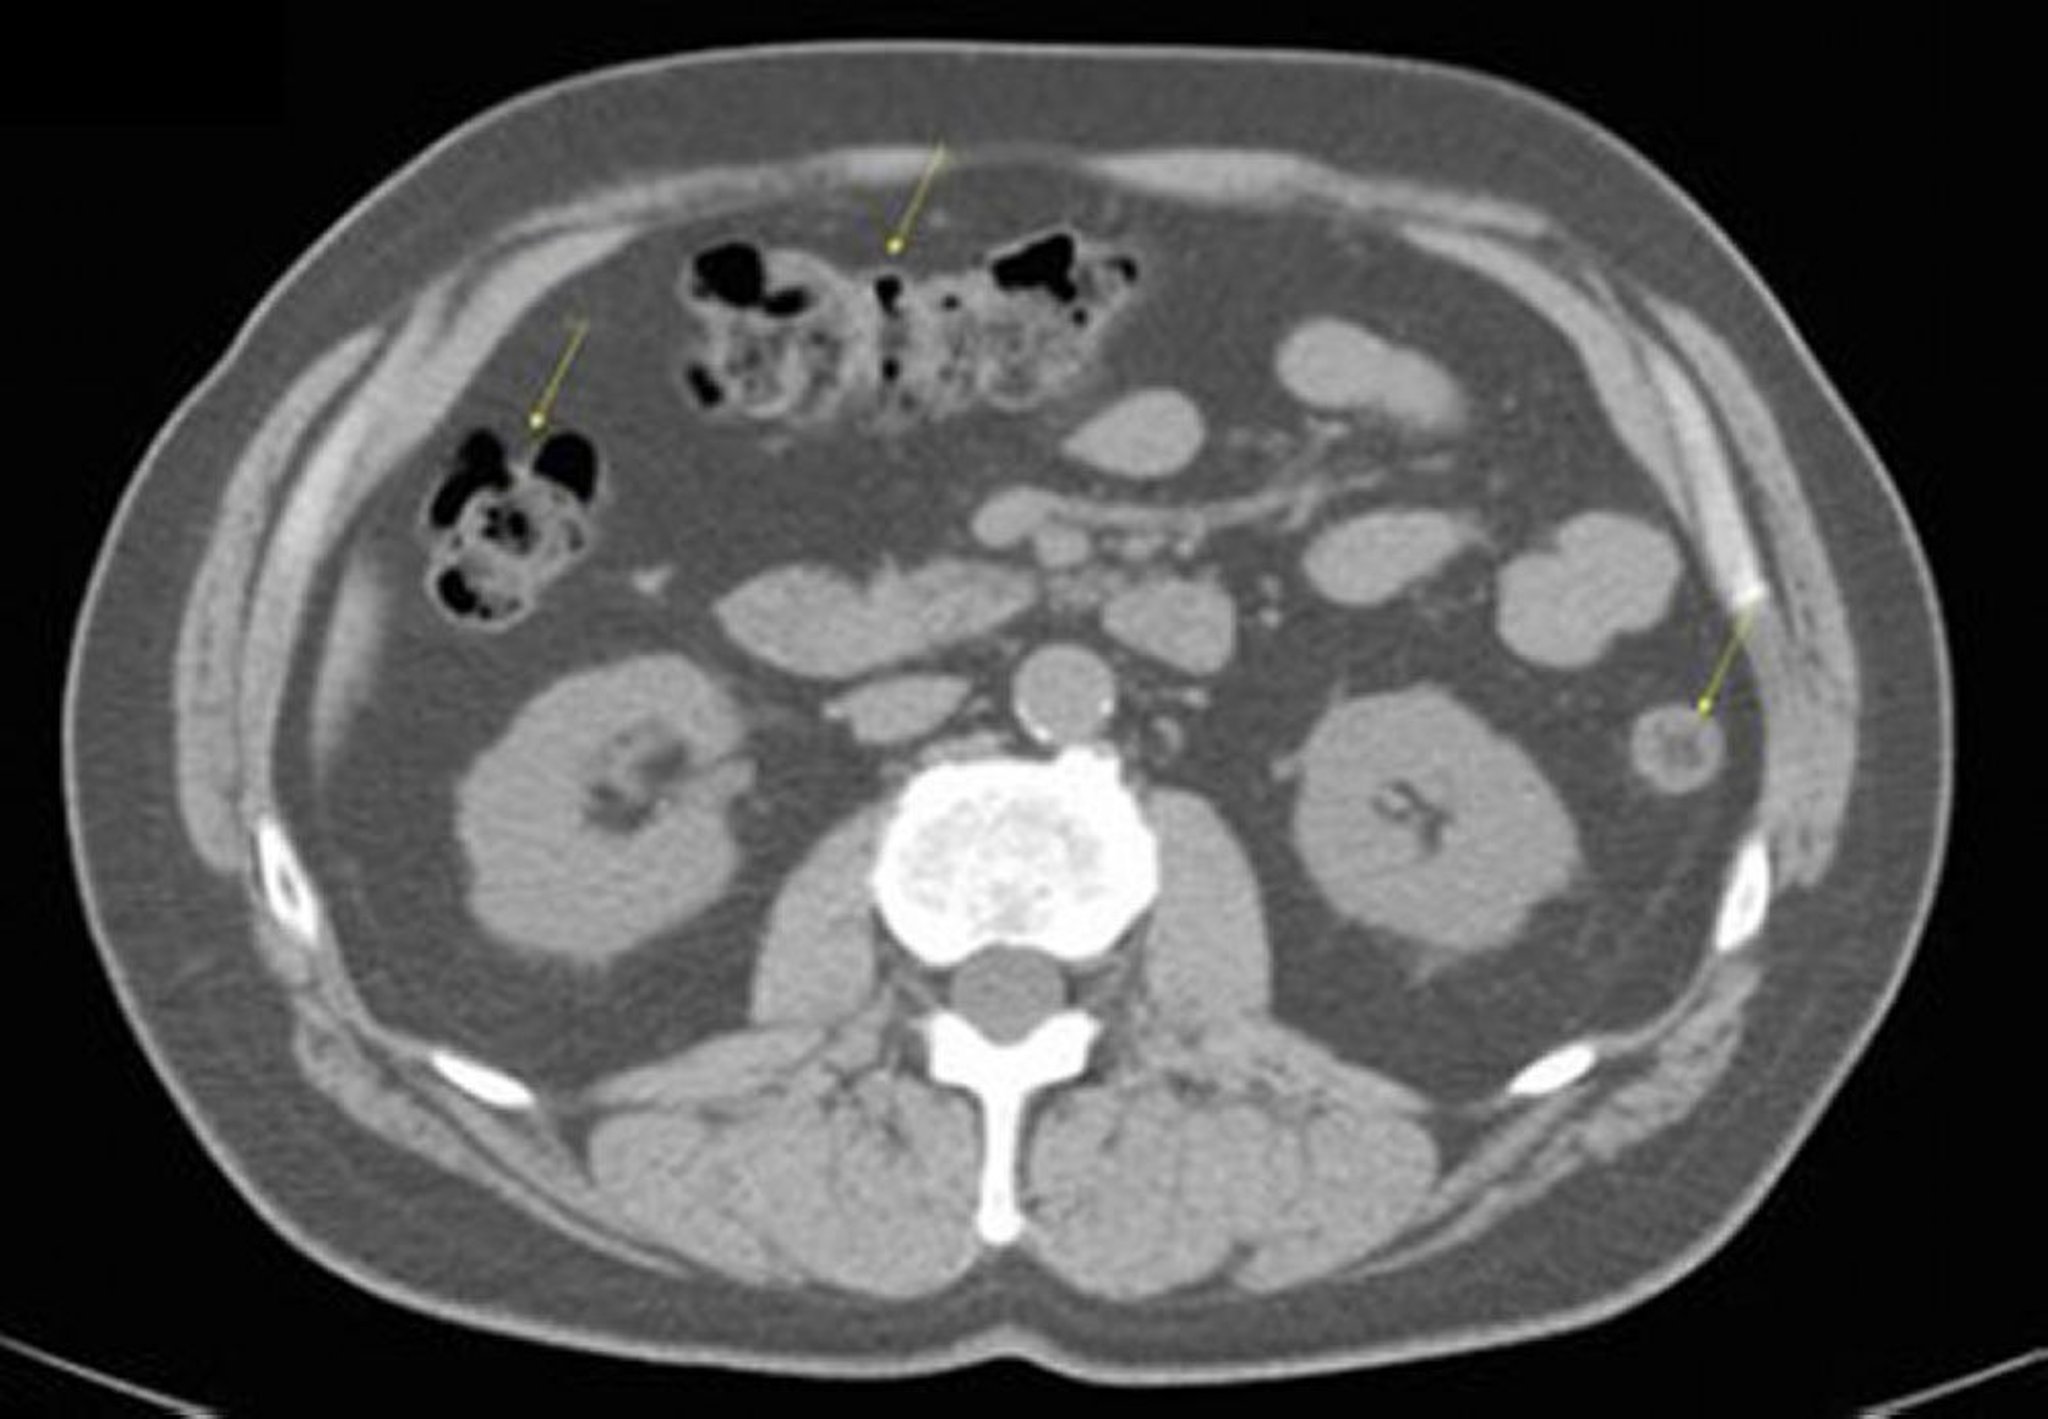

TDM sans contraste de l'abdomen et du bassin montrant une anatomie normale (diapositive 17)

Cette image montre le côlon (flèches).